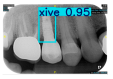

| Image Resolution = 825 × 1200 | ||||

| Test Image 1–4 | ![]() | ![]() | ![]() | ![]() |

| Accuracy | 94.13% | 95.29% | 92.88% | 91.80% |

| Recall | 96.71% | 94.03% | 93.88% | 92.15% |

| Model reference time | 6.57 ms | 7.08 ms | 7.12 ms | 6.43 ms |

| Dentists’ average diagnostic time | 2.78 s | 4.55 s | 7.78 s | 7.23 s |